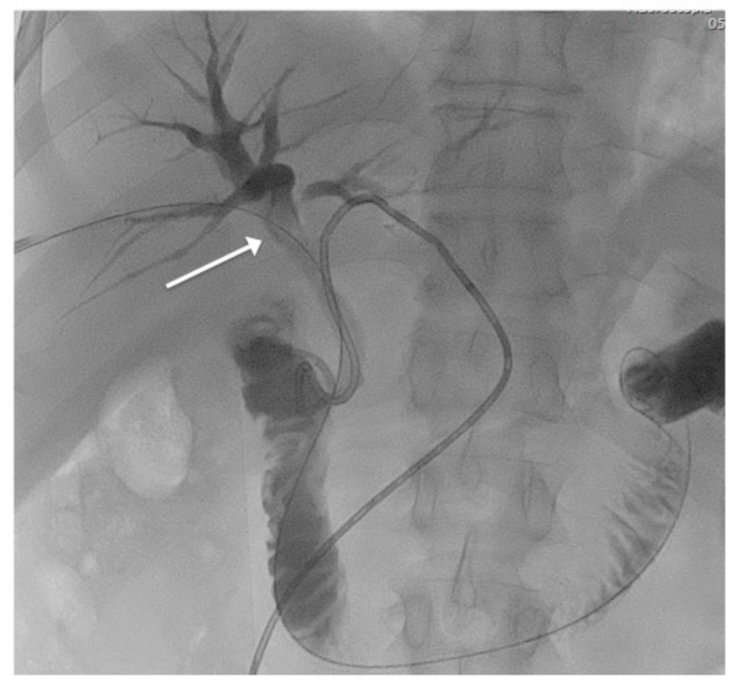

2.1. Patient 1